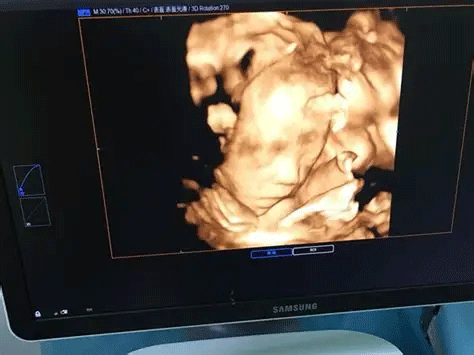

三维彩超,即彩色多普勒超声检查的一种,检查图像呈土黄色,通过多普勒超声仪器发出超声波,对体内各项器官进行成像。三维即其图像是立体的,可以更直观的看到器官的形态,及时发现病变并进行治疗。三维彩超常用于产检,用来判断胎儿的生长发育的情况或是否出现畸形等。

产检中,三维彩超通过测量子宫纵径、子宫体横径、子宫前后径这三条径线来观察胎儿是否正常。以及通过三维立体的成像,可以清晰的显示出胎儿各个内脏器官,以及面部器官、四肢的情况,来简单的判断胎儿是否存在畸形,包括胎儿是否患有先天性心脏病也是能够检查出来的。

三维和四维并不是彩色图片,只是和黑白色有差异,二者呈现的都是土黄色的画面。但三维的成像是静态的,是一张图片,而四维彩超则是动态的,像一张动图一样,并且有的医院会允许刻成光盘带回家收藏起来。

2、检查维度